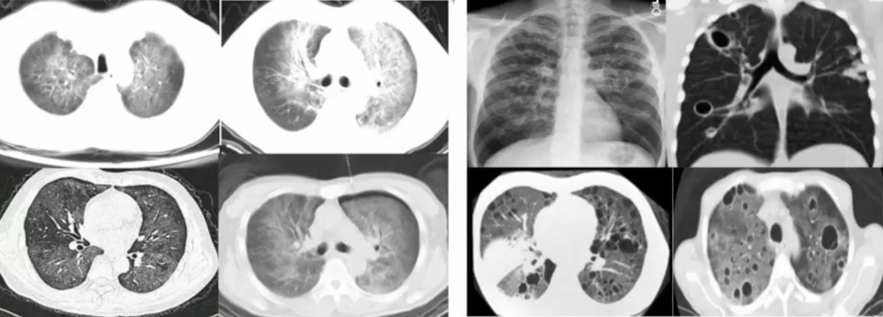

3. 影像学特点(肺孢子菌肺炎)

最常见的肺孢子菌肺炎的影像学表现为双肺对称的磨玻璃影,有部分患者可出现囊状改变、实变或肺纤维化,有时合并气胸。这些影像学变化可以出现在同一患者的不同病程中,或者在同一时间段同时出现。